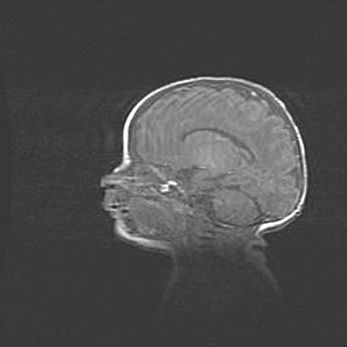

Неполная лизэнцефалия (пахигирия). Открытая гидроцефалия.

Возраст: 17 дней

Вес: 3110 г

Пол: мужской

Окружность головы: 33,5 см

Срок гестации: 35-36 недель

Лизэнцефалия—недоразвитие корковой пластинки и мозговых извилин в результате нарушения миграции нейронов коры. Поверхность мозговых полушарий гладкая. Микроскопически выявляется отсутствие нормальных слоев коры и скопление групп нейронов в подкорковом белом веществе.

Пахигирия—уменьшение числа вторичных извилин. В пораженном полушарии нервные клетки образуют толстый недифференцированный слой с неправильно расположенными нервными волокнами и группами гетеротопных клеток. Нервные клетки незрелые. Белое вещество истончено. При этом нередко аномально развит корково-спинномозговой путь.